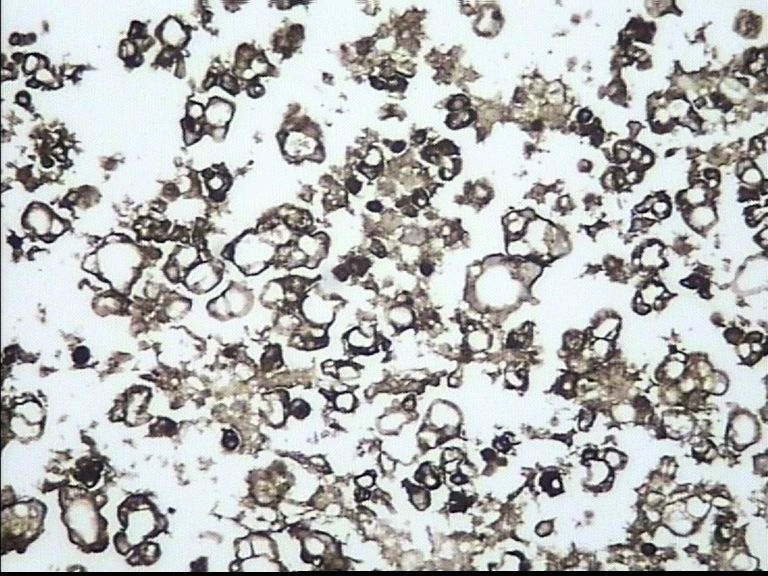

67岁 男 胸水组织块

• 67岁 男 胸水组织块图1

图1

TTF-1

ck7

CEA

肺腺癌细胞

肺腺癌